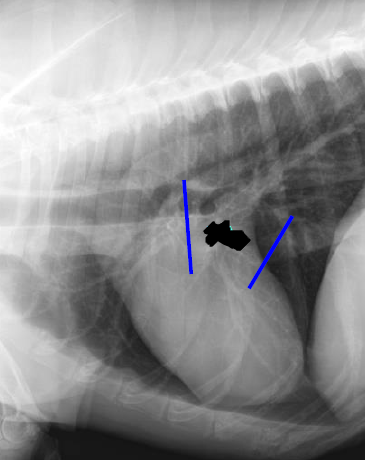

Feline

Left atrium

Left auricle

Left Ventricle

Mass on right side